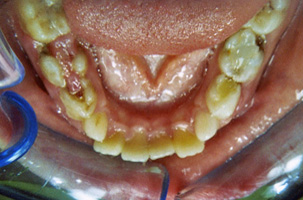

Περιοδοντολογία

Η περιοδοντική νόσος μετακινεί τα δόντια καθώς το κόκαλο που τα υποστηρίζει υποχωρεί σταδιακά. Έτσι τα δόντια εμφανίζουν διαστήματα μεταξύ τους ή/και περιστρέφονται. Η ορθοδοντική θεραπεία επαναφέρει τα δόντια στις ορθές τους θέσεις και τέλος τα ακινητοποιεί ώστε να διασφαλιστεί η μακροβιότητά τους στο στόμα.